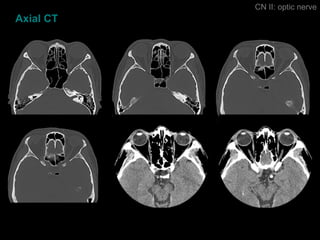

Axial CT CN II: optic nerve

Axial CT CNII: optic nerve